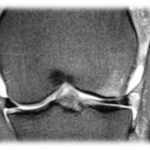

Lesão do Ligamento Cruzado Anterior (LCA) do Joelho

O ligamento cruzado anterior (LCA) é o principal estabilizador do joelho, impedindo o deslocamento anterior da tíbia em relação ao fêmur. Pacientes com lesão do LCA frequentemente relatam um episódio de entorse ou trauma no joelho, seguido de inchaço, dor e, posteriormente, sensação de falseio.

A instabilidade causada por essa lesão pode levar a lesões degenerativas da cartilagem articular a partir de 6 meses. Após 5 anos de lesão, 50% dos pacientes desenvolvem artrose no joelho, e após 10 anos, 75% apresentam esse quadro.

Em 50% dos casos, pacientes com lesão do LCA também possuem lesões meniscais associadas, sendo mandatório investigar essas ocorrências. O exame clínico, com testes como Lachmann e Pivot Shift, possui alta acurácia no diagnóstico.

Tratamento

Atualmente, a indicação de tratamento para indivíduos fisicamente ativos que apresentam instabilidade anterior do joelho é a reconstrução ligamentar com enxertos. Os enxertos mais utilizados são os tendões da pata de ganso (semitendinoso e grácil) e o tendão patelar.

A reconstrução do LCA com tendões flexores (grácil e semitendinoso) é uma técnica que apresenta menor morbidade, pós-operatório menos doloroso e melhor estética, por não envolver um acesso anterior no joelho. Funcionalmente, os enxertos mencionados são equivalentes e têm respaldo na literatura.

Os pacientes são orientados a mobilizar e apoiar precocemente o membro inferior acometido, com acompanhamento de fisioterapeuta e educador físico. Geralmente, são liberados para retornar às atividades físicas de contato após 6 meses.